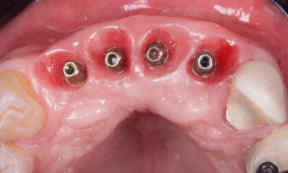

A 55-year-old female patient came to the dental office complaining about the esthetics of her smile, dental absences, and

referring interest in oral rehabilitation with im-plant-supported prosthesis. The clinical exam showed absence of 4 upper incisors and horizontal bone deficiency (Figure 1, 2).

Figure 1: The clinical exam showed absence of 4 upper incisors and horizontal bone deficiency.

Figure 2: The clinical exam showed absence of 4 upper incisors and horizontal bone deficiency.